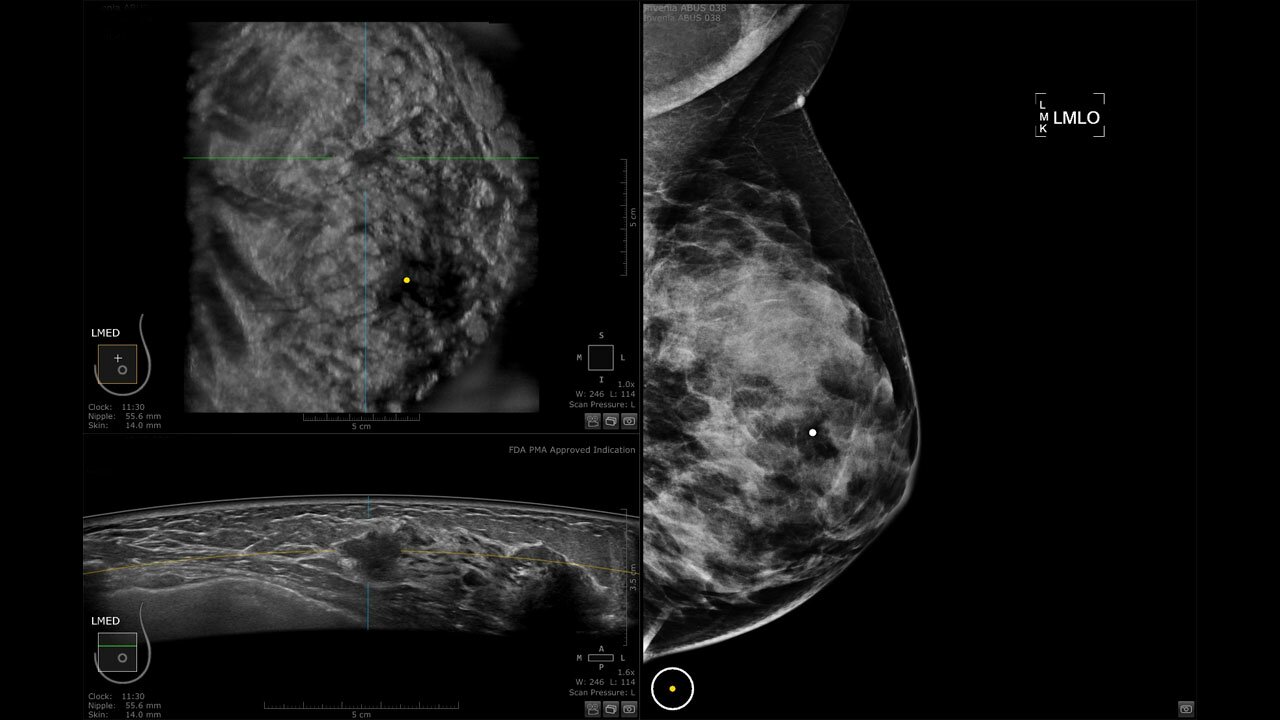

Клинические изображения

• Отображение объемных 3D ультразвуковых изображений, которые состоят из традиционных поперечных и воссозданных коронарных и сагиттальных проекций

• "толстый срез" в коронарной плоскости;

• поперечная;

• сагиттальная плоскость;

• Одновременный просмотр двух изображений для сопоставления в коронарной плоскости